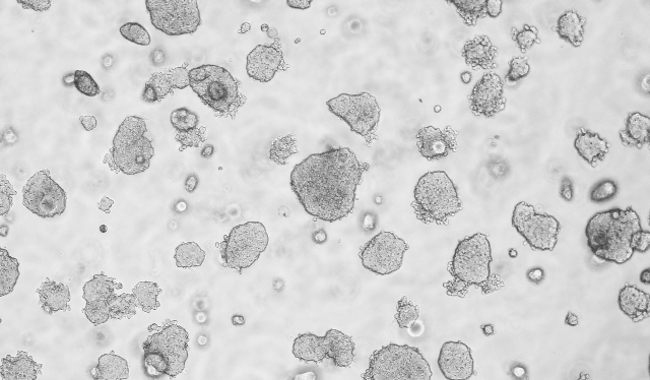

平板克隆形成圖像分析

平板克隆試驗是一種常用的測量細胞生長能力的技術,從開始已知的細胞群體監(jiān)測菌落的形成。菌落的形成需要密集的分裂的原始細胞,所以在整個實驗的細胞或菌落的數(shù)量的量化是細胞的生長潛力的指標。因此,集落形成試驗已成為一種廣泛用于癌癥研究的方法來研究藥物和電離輻射療法對癌細胞增殖的影響。